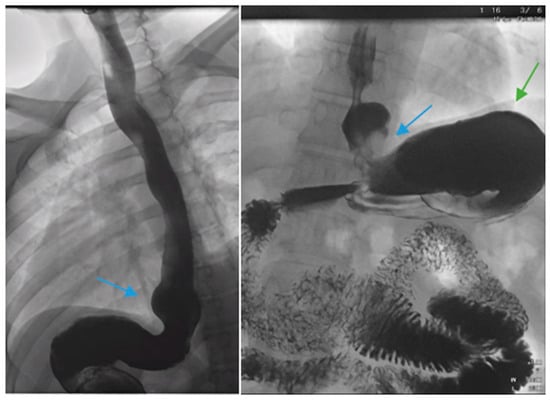

Figure 9.

Laparoscopic image reveals a patient post-sleeve gastrectomy with a defect in the diaphragmatic hiatus (arrow) and subsequent gastroesophageal reflux disease. Image courtesy of Dr. Brian Louie, Chief of Thoracic Surgery at Swedish Medical Center in Seattle, Washington, USA.

Figure 10.

Laparoscopic image demonstrates hiatal hernia repair and successful placement of a magnetic sphincter augmentation device (arrow) around the esophagus in a patient post-sleeve gastrectomy with gastroesophageal reflux disease. Image courtesy of Dr. Brian Louie, Chief of Thoracic Surgery at Swedish Medical Center in Seattle, Washington, USA.